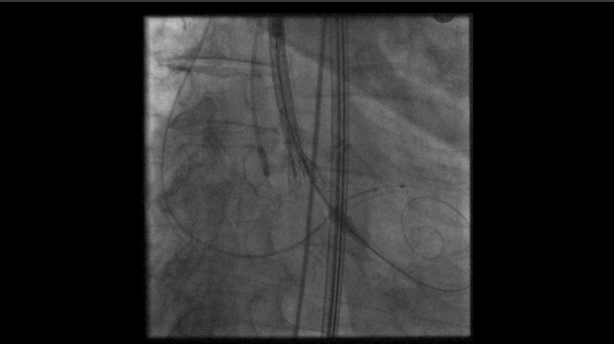

我們會於鼠蹊部動脈,置入導絲與導管,然後沿著導絲將合適患者大小的新瓣膜放入,再取出氣球、導管與導絲,最後檢查患者股動脈與觀察術後生命徵象。整個手術時間約1小時,傷口約3cm,住院時間也約3到4天。

在一些合適的病友,甚至能在局部麻醉之下,即可接受主動脈瓣膜的置放。本項技術皆於本院新建之整合型手術室(hybrid operation room)進行,且與歐美同步使用最新之Philips Epiq 3D重組影像來輔助心導管瓣膜手術的置放。這項手術需要心臟內、外科的團隊通力合作,術前仔細的評估與術後密切的追蹤。